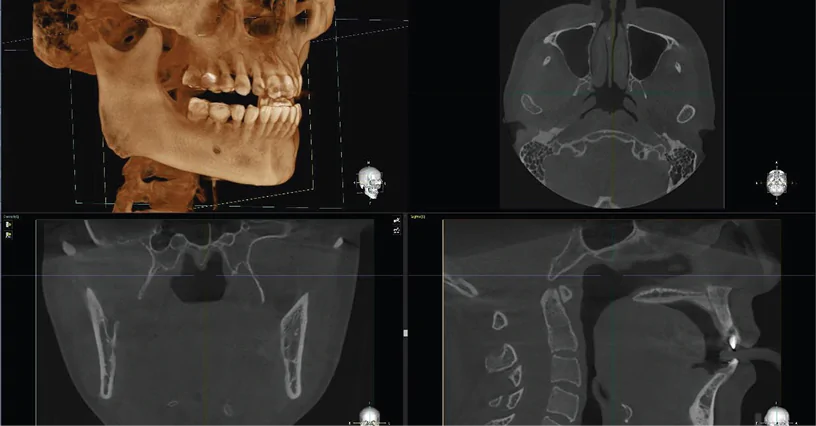

Analiza tridimensională completă este realizată prin reconstrucții multiplanare (MPR – axial, sagital, coronal), secțiuni transversale (cross-sectional) și vizualizare volumetrică 3D, oferind o perspectivă corectă asupra volumului osos și a relațiilor anatomice. În implantologie, aceste funcționalități permit poziționarea implantului atât din punct de vedere chirurgical, cât și protetic, reducând discrepanțele dintre planificare și execuție și transformând tratamentul într-un proces predictibil.

Dentium Rainbow™ CT 2 în 1 este optimizat pentru integrarea în fluxuri digitale moderne, permițând planificare implantologică 3D, evaluarea volumului și densității osoase, precum și simularea poziționării implantului. Compatibilitatea cu ghidurile chirurgicale facilitează transferul fidel al planificării în execuția clinică, contribuind la creșterea preciziei și reducerea erorilor operatorii.

Un rol central îl are software-ul Dentium (Rainbow 3D Viewer + Image Viewer), care integrează funcții avansate într-o interfață intuitivă. Acesta permite reconstrucții MPR, analiză volumetrică 3D, măsurători precise și planificare chirurgicală, optimizând fluxul de lucru și reducând timpul necesar pentru interpretare. În practică, acest lucru se traduce prin eficiență crescută, reproducibilitate și integrare reală în rutina clinică.